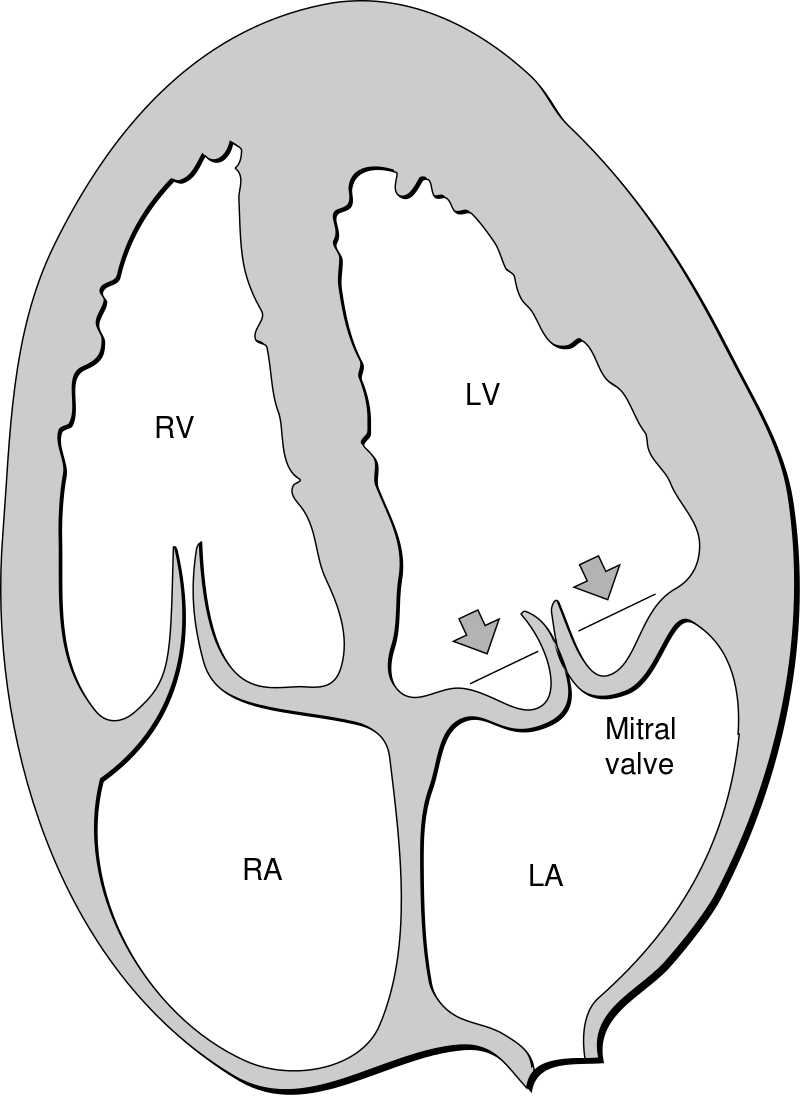

The mitral valve is the most affected cardiac valve.

Small vegetations accrue on the valve along the lines of closure that result in mitral regurgitation.

Chronic rheumatic heart disease develops when rheumatic fever-related valve scarring leads to stenosis with the classic fish-mouth appearance.

In chronic rheumatic heart disease, the chordae tendineae and cusps thicken as a result of the mitral valve being involved almost always.

Mitral regurgitation occurs when blood flows from the left ventricle into the left atrium during systole and is mainly caused by mitral valve prolapse.

The narrowing of the mitral valve orifice is known as mitral stenosis.

Mitral stenosis is associated with persistent rheumatic valve disease.

Clinical findings of mitral stenosis include:

- An opening snap followed by a diastolic rumbling

- Volume overload that causes the left atrium to enlarge